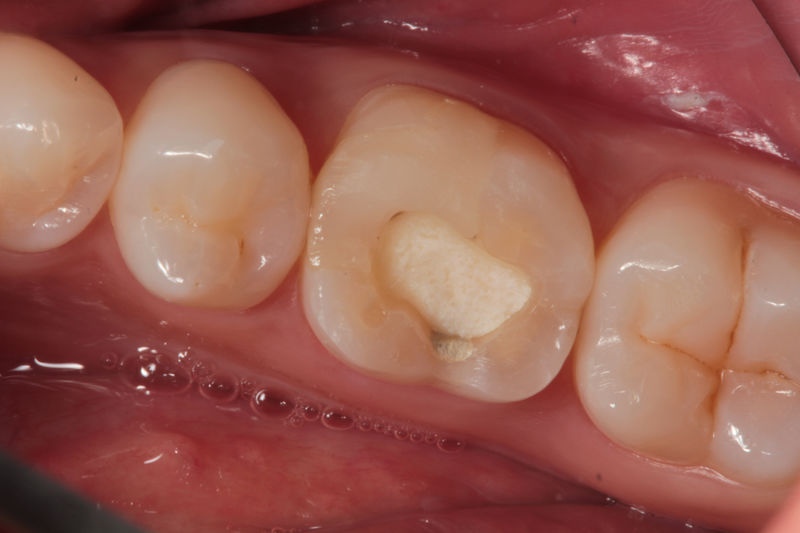

Disciplina fundamental de la Odontología enfocada en el diagnóstico, prevención y tratamiento restaurador de las piezas dentales que han sufrido daños. Su objetivo principal es devolver al diente su equilibrio biológico, funcional y estético cuando su integridad ha sido alterada. Resinas directas, incrustaciones, coronas.

Restauraciones fabricadas en el laboratorio con materiales estéticos, los cuales cubren de manera parcial dientes posteriores. Se utilizan primariamente para restaurar dientes con caries, fracturas y/o defectos amplios. Para poder enviar el caso al laboratorio se toman impresiones utilizando materiales de impresión o técnicas modernas digitales.